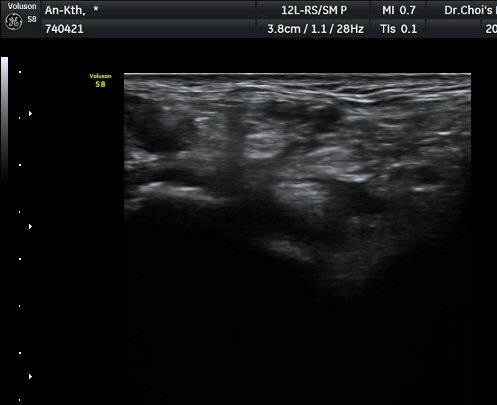

°üÂûµÈ´Ù(±×¸² 1, 2, 3). ±ä¾öÀÚ±¼°î°Ç Á¾´Ü¸é°Ë»ç¿¡¼­ ±ä¾öÁö±¼°î°ÇÀÇ ºÎÁ¾°ú

°Ç ½ÉºÎ¿¡ ¼ö¾×Àú·ù°¡ °üÂûµÊ(±×¸² 4).